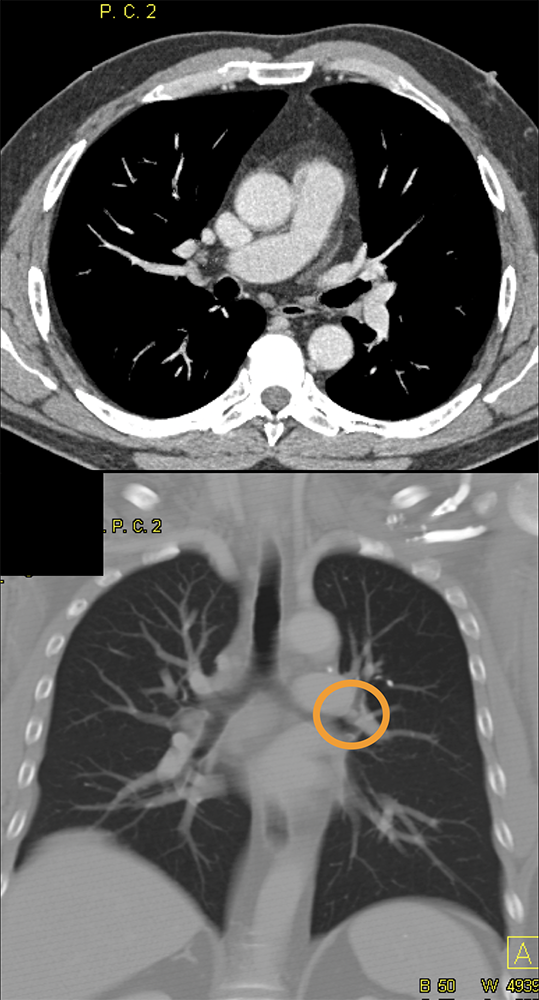

SOB and Hemoptysis ![]() |